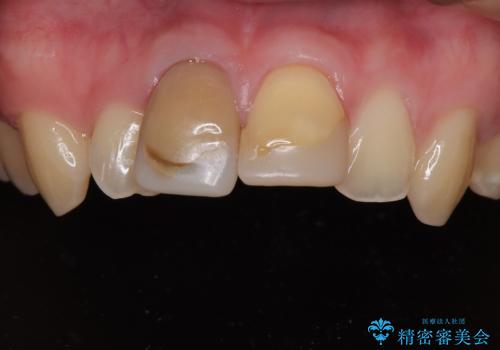

転倒時に前歯2本が折れてしまい、すでに根管治療(神経の治療)が行われている状態でした。

噛み合わせを改善するための矯正治療をご提案しましたが、患者様のご希望により矯正治療と根管治療の再治療は行わず、ファイバーコア(土台)+オールセラミッククラウンによる補綴治療を選択しました。

審美性と強度を両立させるため、透明感のあるオールセラミッククラウンを採用し、周囲の天然歯に自然に調和するよう色調・形態を調整しました。